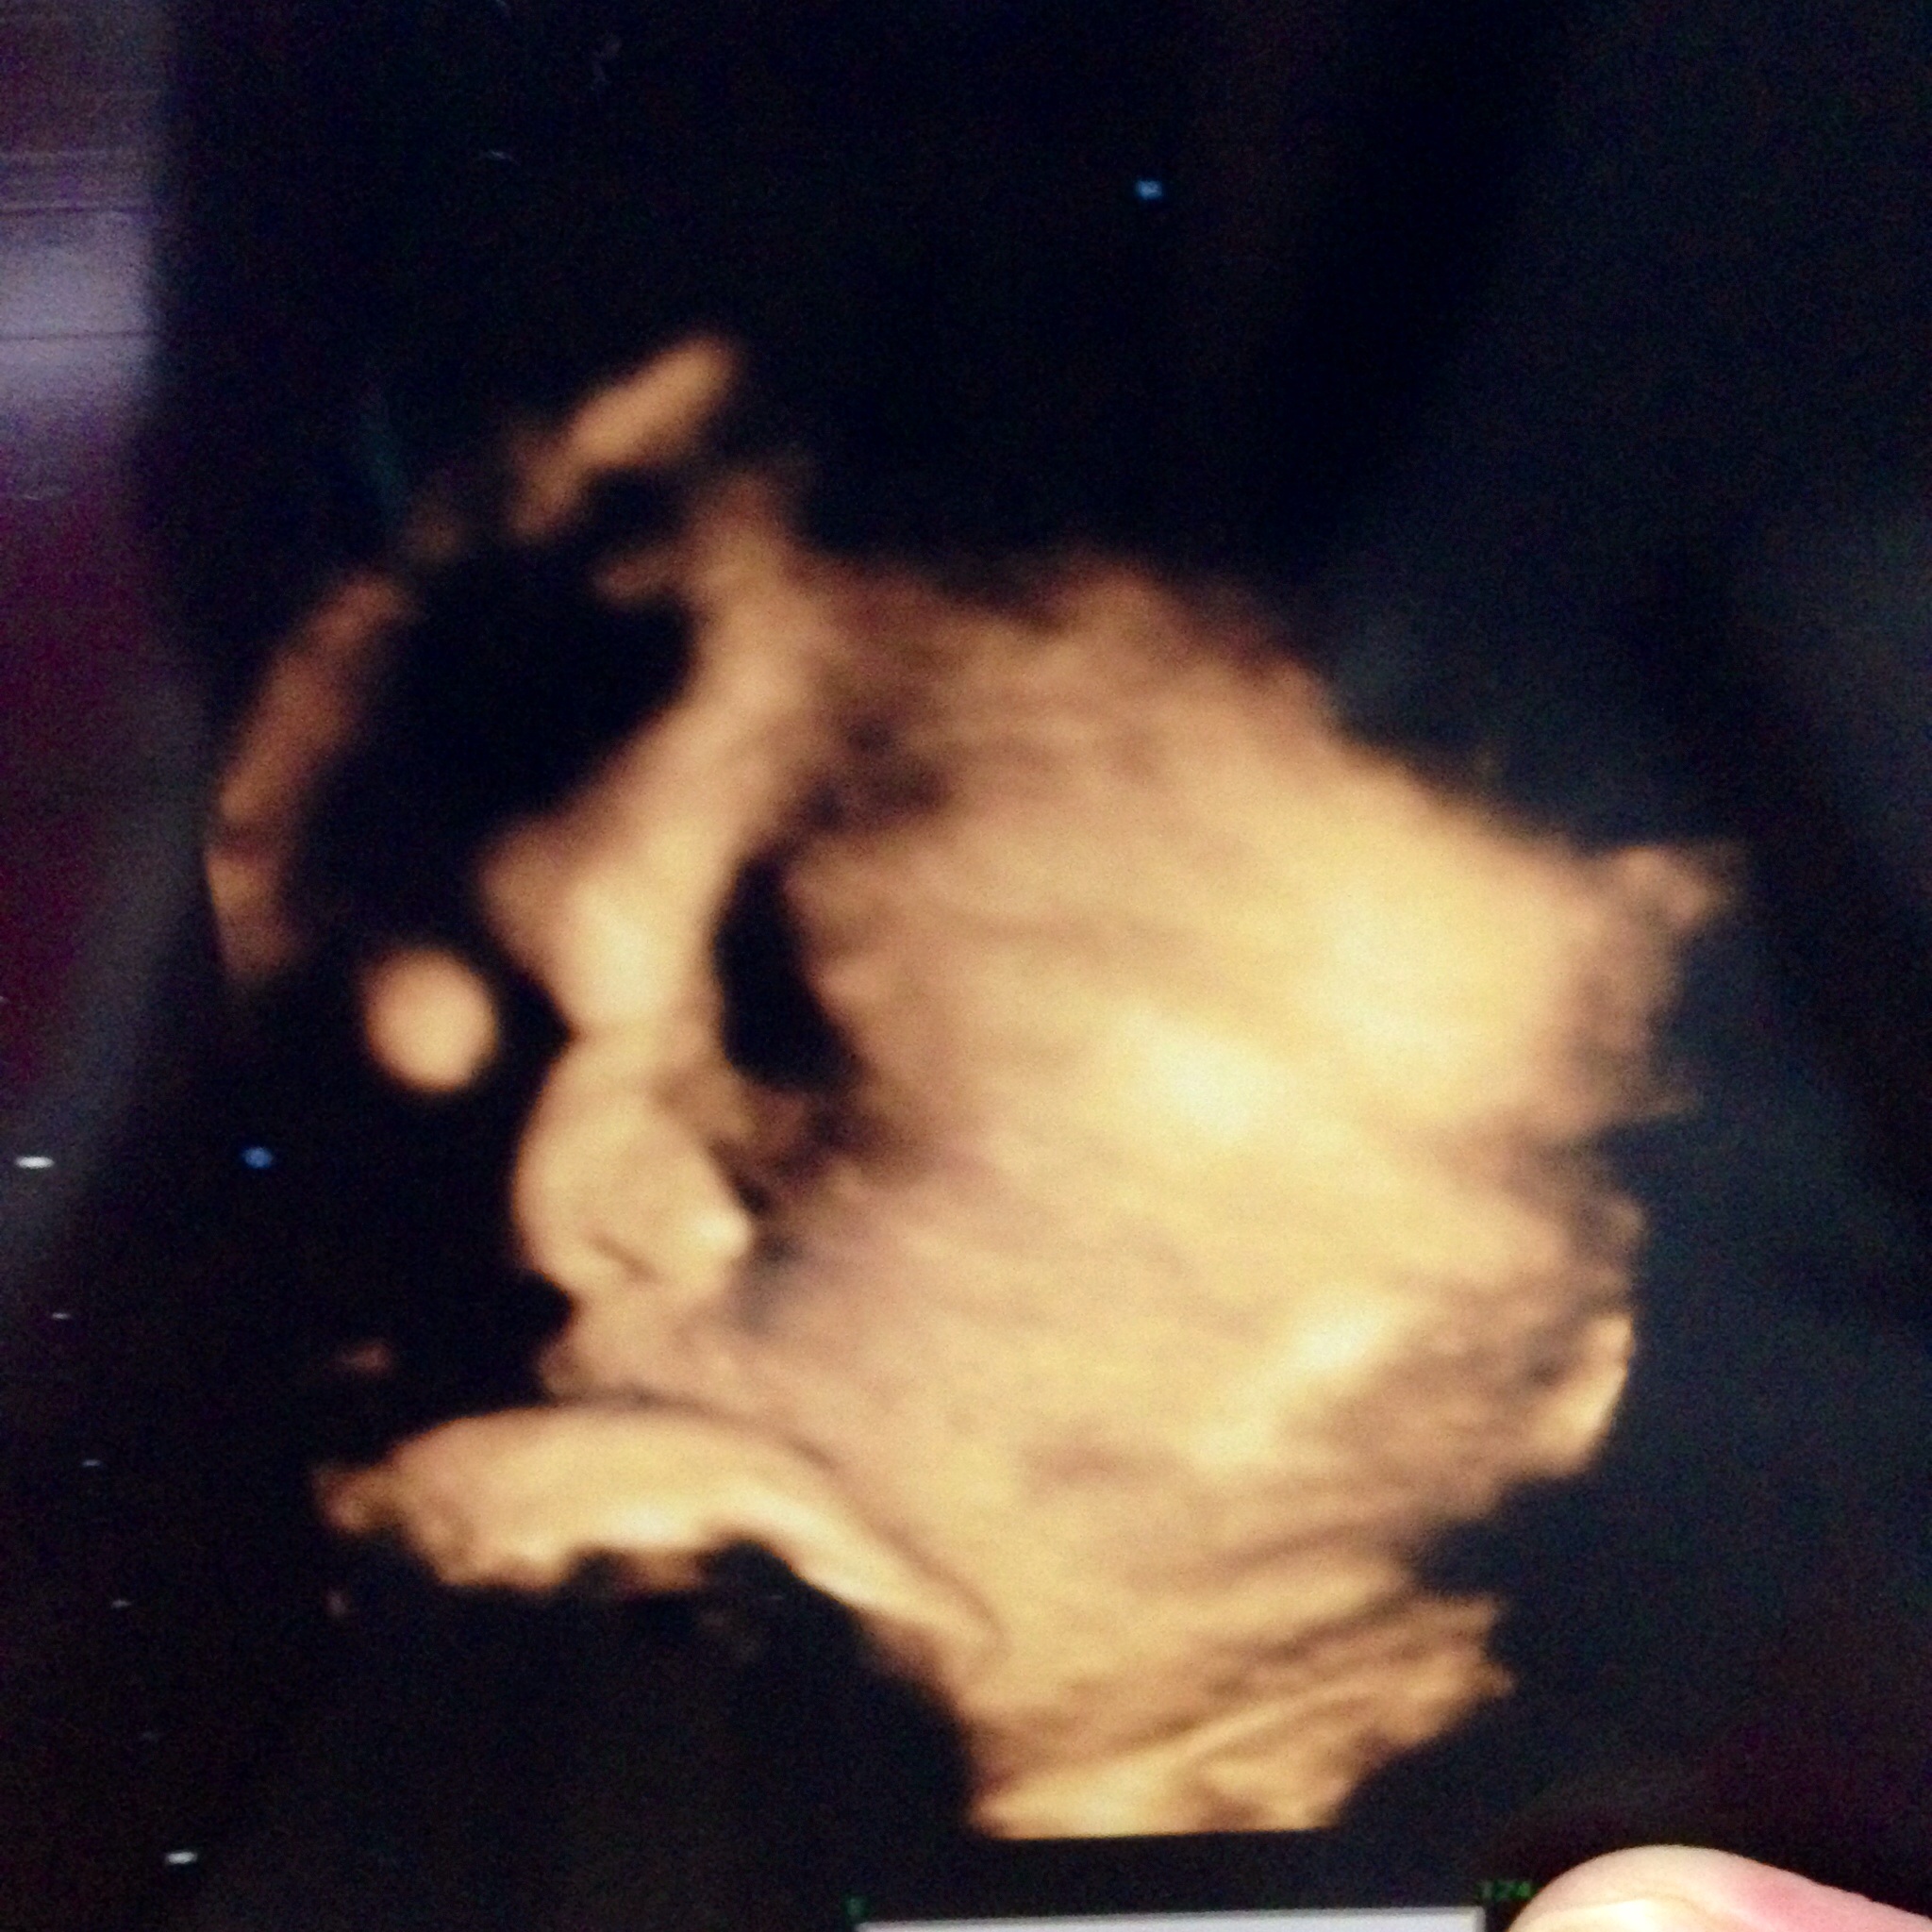

もう上手くエコーに映らなくなってきたよーーぶしゃいく。

推定3021g

あ、この産院には先生が3人いるのですが、前に聞いた先生じゃなかったから、また「うちの子、鼻 高いですよね!」って聞いちゃいました。←しつこい笑

だって嬉しいんだもん。